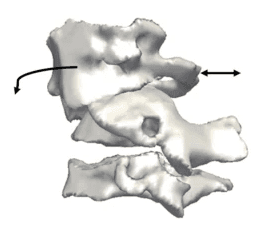

3D reconstruction of the cervical vertebra. Arrows depict the deformity secondary to anterolisthesis of C1.